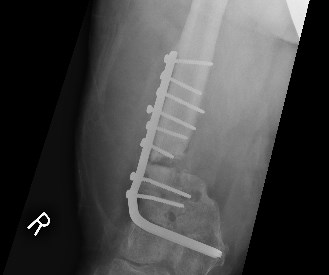

The latest attempt to stick my leg back together................ looks like a bit of old curtain rail

Not so much if it's stainless, or even (which they do sometimes these days) titanium. At least mine never do...Fraser wrote: That's going to send the airport metal detector off the scale!!